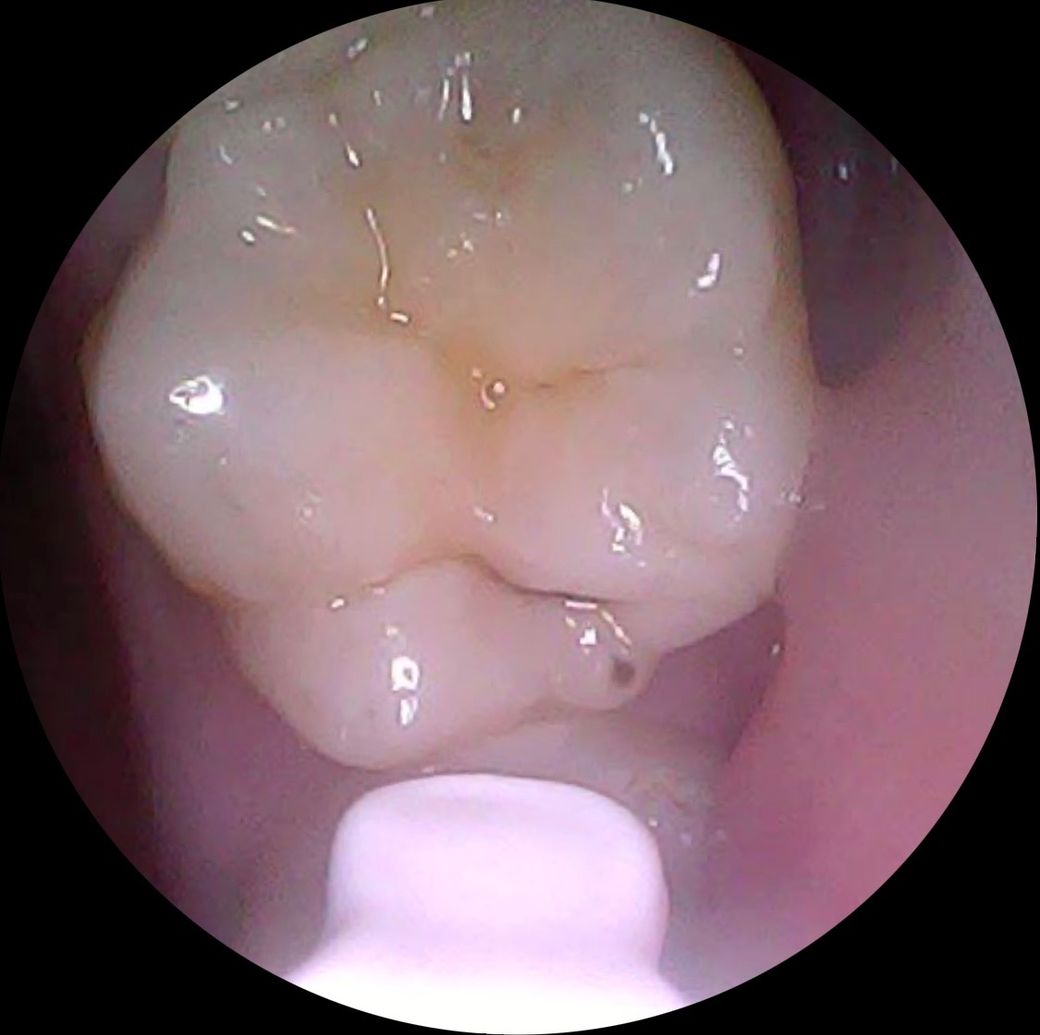

전체 어금니 상태인데, 아래 치아들을 제외하면 깨끗합니다.

• 3번 째 사진

엑스레이를 찍어봐야 정확히 알겟지만,첫번째 치아는 충치가 상당히 진행된거 같고 나머지 치아의 충치는 간단한 충치 같습니다.

2,3,4,6번째는 충치가 그렇게 크진 않습니다 치료가 필요한 정도일지는 엑스레이 찍어봐야합니다